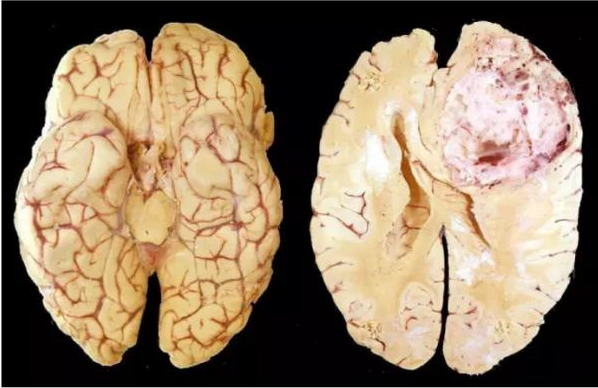

胶质母细胞瘤患者的脑组织

胶质母细胞瘤(GBM)就是我们上面说的“顽固分子”之一。它对放疗的敏感度不高,对化疗的呢,也需要多种药物、大剂量的冲击,才能取得较好的效果,但是大剂量的化疗药物所带来的不良影响想必大家也都猜得到。而免疫疗法虽然能将患者的生存率从一年多提高到五年,但是显然大家还希望有更多的突破,于是就有研究人员盯上了“化疗+免疫治疗”这个联合疗法。(下方图片小高能)